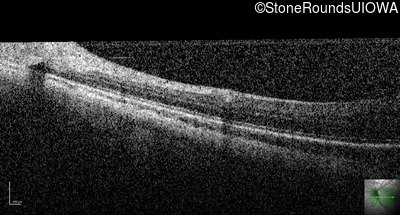

Infrared Fundus Photograph - Left - 20/80

Exemplar